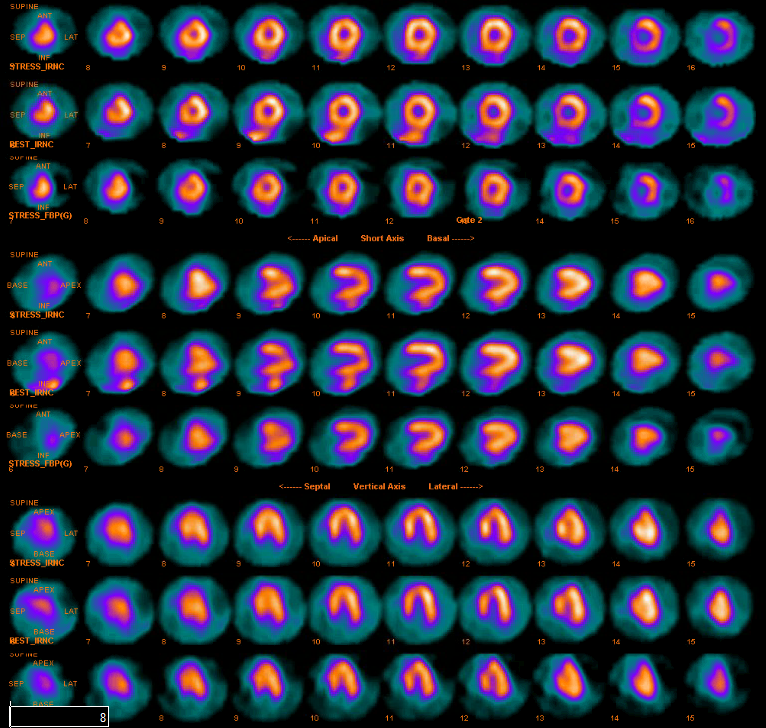

Neurogenic stunned myocardium is a triad of reversible left ventricular dysfunction, electrocardiogram changes and elevation of cardiac enzymes. Clinically, this provides diagnostic challenges in the setting of subarachnoid hemorrhage (SAH) due to the diagnostic uncertainty. The pathophysiological mechanisms for neurogenic stunned myocardium have included hypothalamic and myocardial perivascular lesions. More recently, alternative research has focused on myocardial microvascular dysfunction and genetic polymorphisms. Management has remained largely supportive with case reports citing the benefits of inotropes and intra-aortic balloon pumps in the setting of cardiogenic shock complicating NSM. When NSM follows SAH there are numerous complications, including pulmonary edema, arrhythmias and prolonged intubation, which can impact outcomes and increase morbidity and mortality. This highlights the need for accurate and timely diagnosis of NSM which has remained a clinical challenge. We report a case of a 52-year-old patient who presented to the ICU with complaints of atypical chest pain without neurologic complaints or lateralizing symptoms. She was admitted to the ICU for ongoing chest pain with concurrent ECG T-wave inversions. Within 24 hours she developed lateralizing neurologic signs and altered mental status with subsequent imaging revealing evidence of a SAH. We describe characteristics and outcomes of NSM in this patient with aneurysmal associated SAH.References